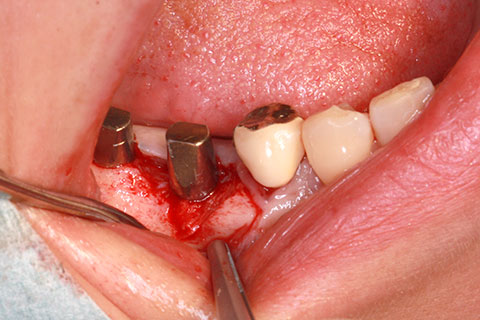

• 症例2

治療前

インプラント埋入時

治療後

年齢・性別

57歳男性

治療期間

3ヶ月

抜歯

なし

治療費

154万円

備考

左上5.6.7 及び左下6.7欠損

治療内容

左上5.6.7と左下6.7欠損部にインプラント埋入

施術の副作用(リスク)

オペによる知覚障害。インプラントによる歯肉炎。インプラント脱落。